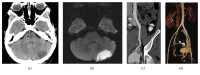

This is a case of choriocarcinoma that did not regress after chemotherapy treatment. A 30-year-old female patient (gravida 2, para 2), presented to our ER with stroke and persistent mild pelvic pain 2 months after a Caesarean section. Computed tomography (CT) revealed an ischemic left hemicerebellar region and a hypervascular mass in the pelvic region. This mass was not present on routine fetal ultrasound during pregnancy. The lesion was treated by chemotherapy after closure of a foramen ovale and insertion of an inferior vena cava (IVC) filter. After that, 2 courses of EMACO (Etoposide, Methotrexate, Actinomycin D, Cyclophosphamide, and Vincristine) chemotherapy regimen were given. Posttreatment CT showed the hypervascular mass without any changes. Arteriography showed the arteriovenous fistulae that were embolized successfully with plugs, coils, and glue. Embolization was considered due to the risk of acute hemorrhagic life-threatening complications. Eight chemotherapy courses were added after embolization. Treatment by endovascular approach and reduction of the hypervascular mass can be a valuable adjunct to chemotherapy treatment of choriocarcinoma.